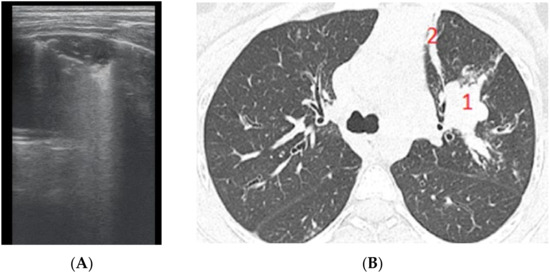

Subpleural consolidation were detected by CT scan (Figure 4) in 33.3% of patients, and confirmed by LUS in 31.5% (Figure 3).

Figure 3. LUS: subpleural consolidation of 1.75 cm/0.78 cm, surface of 0.96 cm2 (score 4), without bronchogram, with adjacent B lines (2 points); A lines also present, examination of left posterior hemithorax.

Figure 4. CT scan of the same patient, with various types of bronchiectasis: (1) cylindrical bronchiectasis with moderate bronchial wall thickening; (2) varicose bronchiectasis; and (3) a round/spiculated consolidation, corresponding to previous LUS consolidation. CT score = 62.